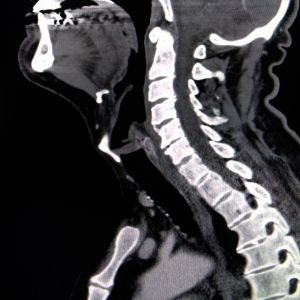

Head & Neck CT Scan

A CT scan of the head and neck helps diagnose neurological issues, trauma, and sinus problems with detailed imaging.